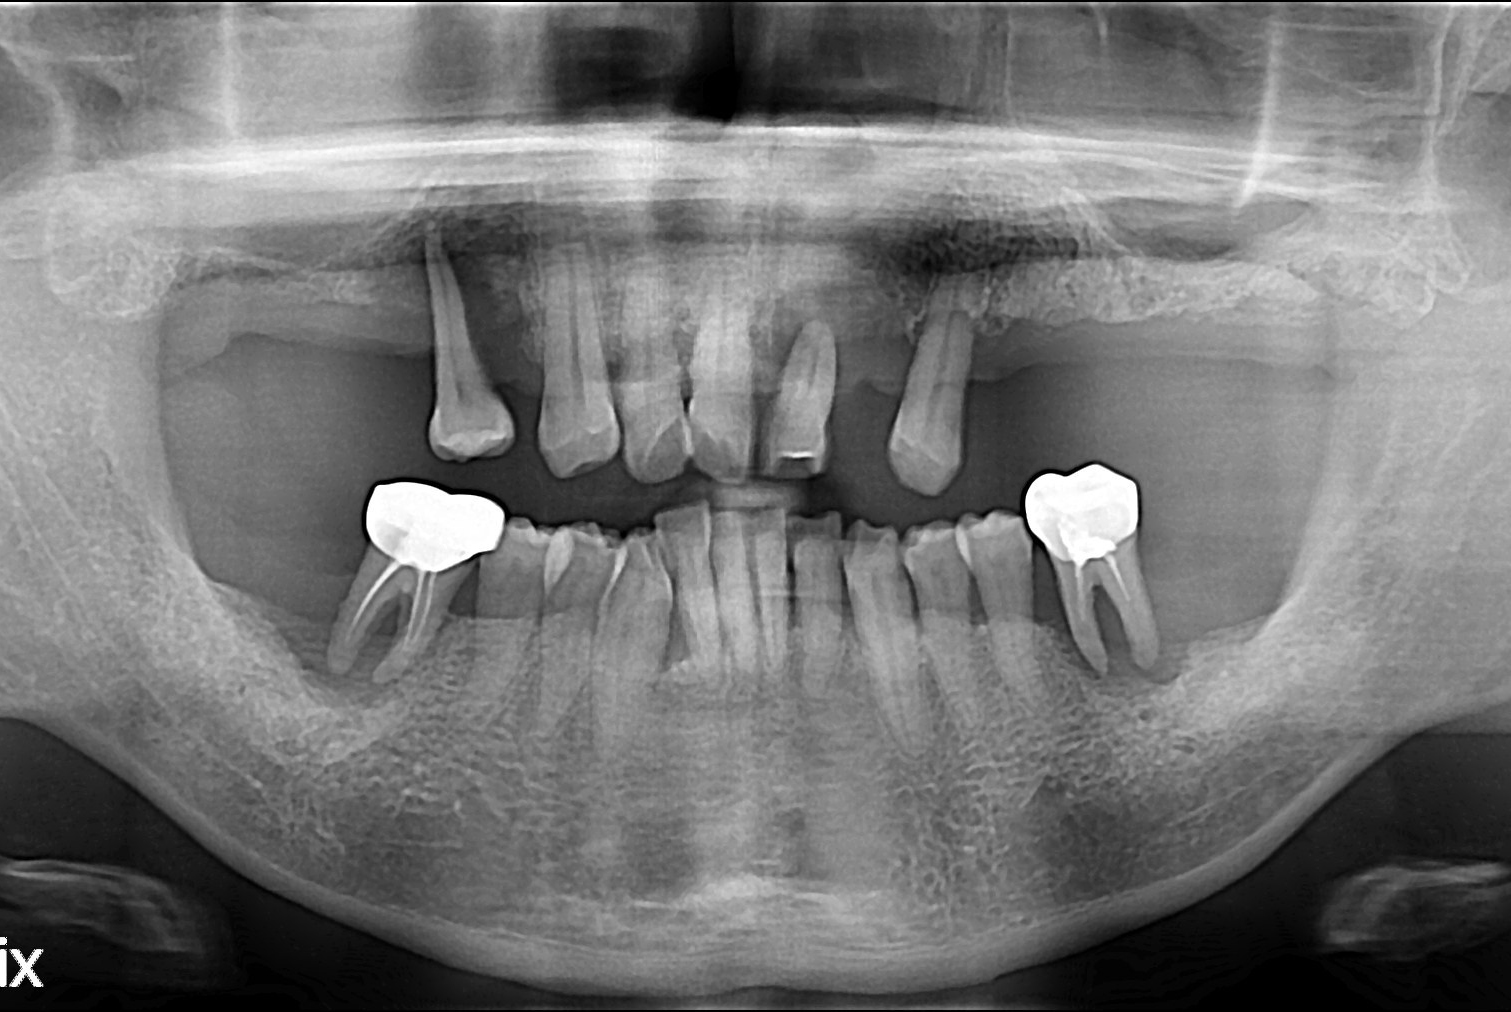

치료전 : 2019-04-05

황채화 후.jpg

세종치과는 많은 환자와 다양한 케이스를 바탕으로 항상 편안한 임플란트 수술을 제공하고자 노력하고,

오래동안 튼튼히 쓸 수 있는 임플란트 수술을 가장 큰 목표로 삼고 있습니다